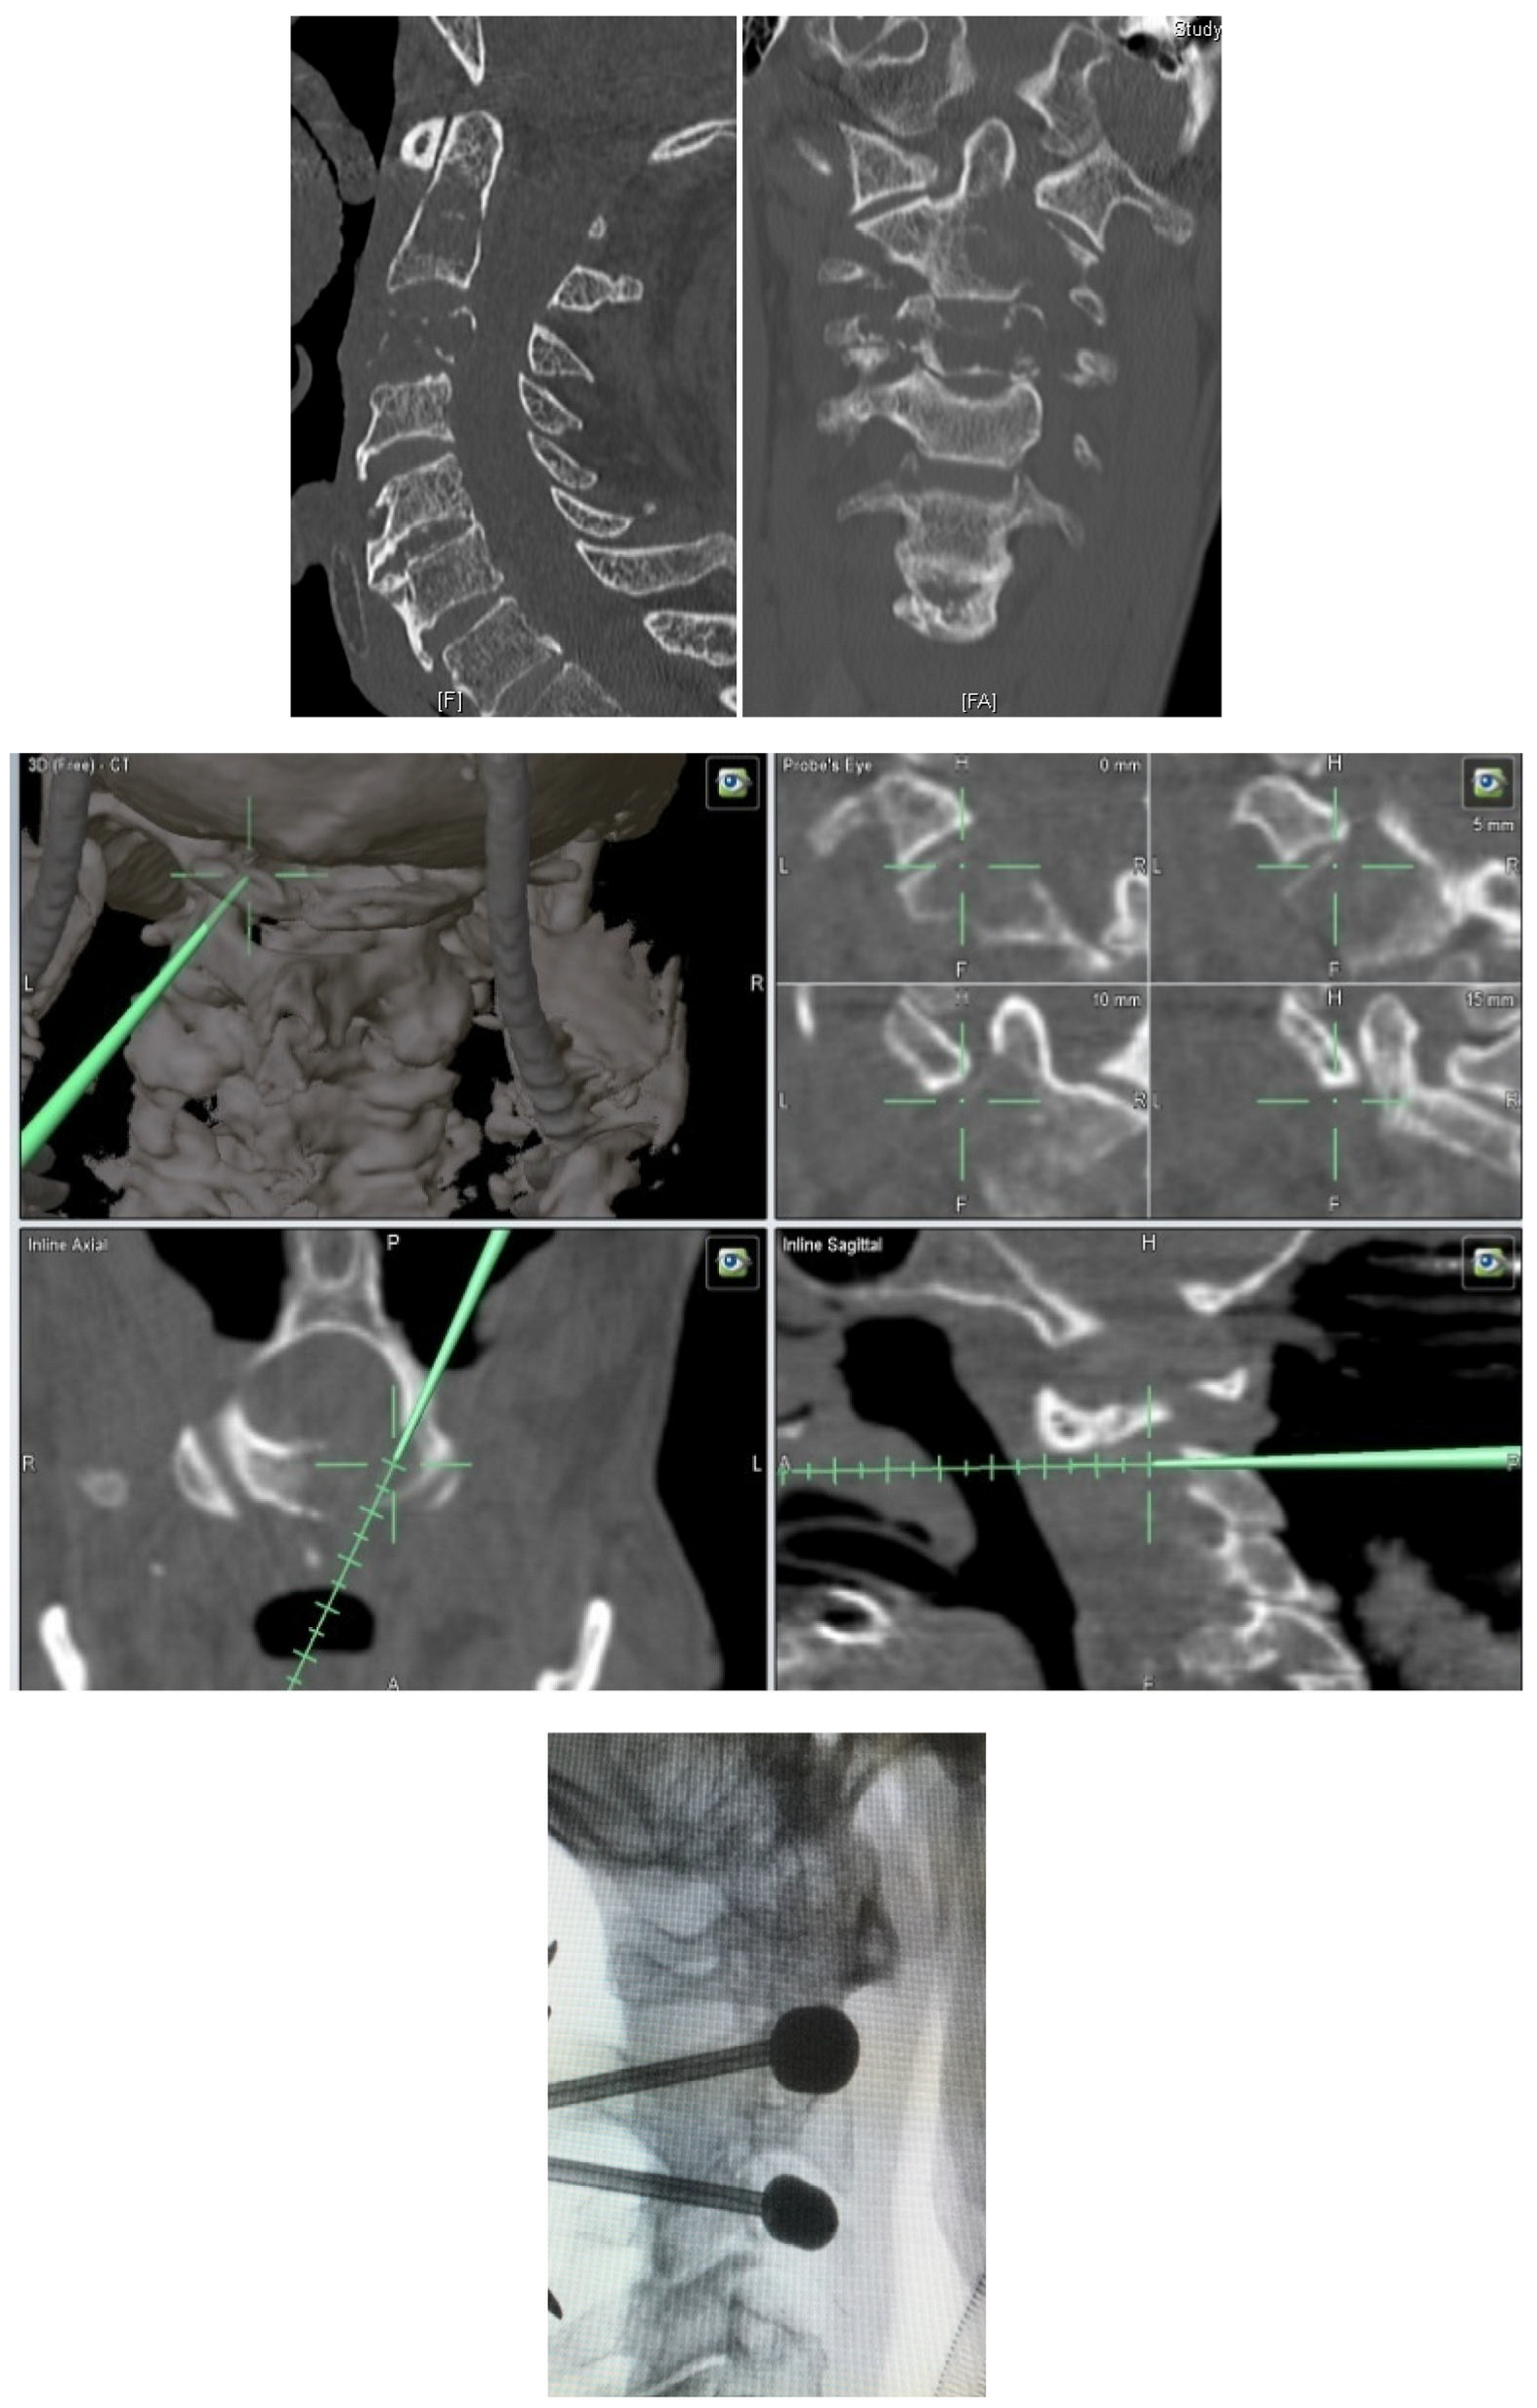

- Posterior percutaneous kyphoplasty for cervical spine metastases (Figure 2); case of C2-C3 kyphoplasty.

- Metastatic lesions of C1 are extremely rare, and their treatment by percutaneous cement augmentation is considered to be a technically challenging procedure due to complex anatomy. We also performed percutaneous kyphoplasty in a painful osteolytic lesion located on the left lateral mass of C1 through a posterolateral approach using a 3D CT scan intra-operative navigation system and fluoroscopy (Figure 3) [22].